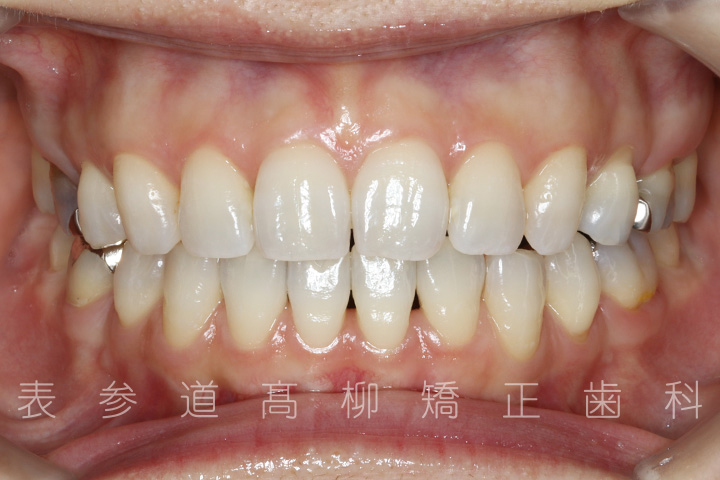

口呼吸と舌癖で前歯が咬み合わない患者様の症例をご紹介いたします。

・前歯部開咬

・上顎前突(前歯の前方傾斜)

・上下前歯部叢生(凸凹歯並び)

・口呼吸、舌癖

術前術後の比較